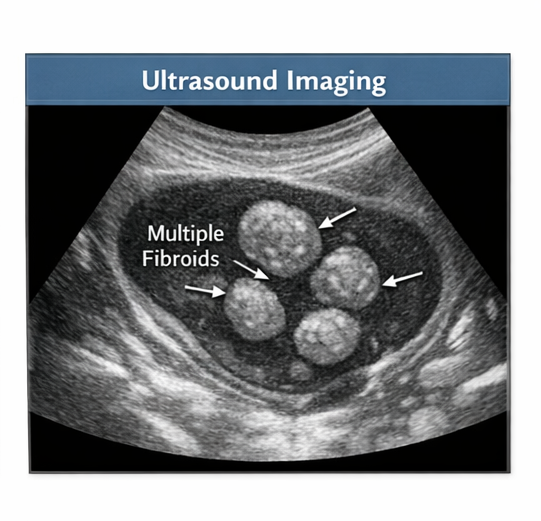

Pelvic Ultrasonography

Transabdominal and transvaginal ultrasound revealed an enlarged uterus with multiple well-defined hypoechoic masses arising from the myometrium. The largest lesion measured approximately 5.2 × 4.8 cm and was located in the anterior uterine wall, consistent with an intramural fibroid.

Two smaller fibroids measuring 2–3 cm were noted in the posterior wall and fundal region. The endometrial cavity was mildly distorted but not significantly compressed. Both ovaries appeared normal.